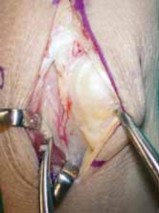

A BTECH FIG 3 • A, B. Drawing and corresponding clinical picture showing inset of the vascularized bone graft into the prepared lunate. Note the proximal–distal orientation of the cortex. (B: Copyright Thomas R. Hunt, III, MD.)